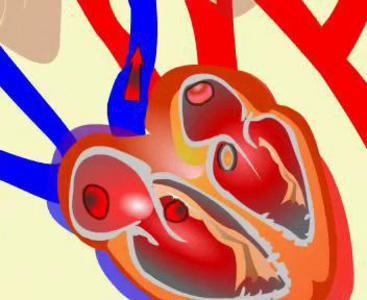

keringési szervek: szív

humán keringési rendszer magában, továbbá a artériák, vénák és hajszálerek, a szív. Ez egy izmos szerv, belül üreges, és amelynek egy kúpos alakú. Szív, fekvő a mellüregben, áll rendelkezésre a szívburok álló kötőszövet. Bag biztosítja az állandó nedvesítő a felszínen a szív, és fenntartja a rendelkezésre állás csökkenése. A fal a szív van kialakítva három rétegből áll: a szívbelhártya (belső), szívizom (középen) és epicardialis (külső). Szerint a szerkezet a szívizom némileg emlékeztet a harántcsíkolt izom, de van egy különlegessége - a képesség, hogy automatikusan csökken, függetlenül a külső körülmények. Ez az úgynevezett automatizmus. Lehetővé válik a speciális idegsejtek, amelyek megtalálhatók az izom és termel ritmikus gerjesztés.

A szerkezet a szív

A belső szerkezet a szív a következő. Meg van osztva két részre, jobb és bal, egy szilárd fal. Minden fele két hadosztály - pitvar és a kamra. Össze vannak kapcsolva egy lyukon keresztül látva egy visszacsapó szelep, amely megnyitja a kamrai oldalán. A bal felét a szív szelep két szárnya és a jobb - három. A jobb pitvar a vér jön a felső, az alsó az üreges, és a koszorúér vénák a szív, és a bal - a négy tüdővéna. A jobb kamra ad okot, hogy a pulmonalis törzs, amely két részre oszlik, a vért a tüdőbe. A bal kamra küldi a vért a bal aortaív. A határokat a kamrák, pulmonalis és az aorta félhold alakú szelep van elrendezve a három szelep egyes. Ezek hordozzák a lezárás lumen aorta és pulmonalis törzs és halad a vérereket, és megakadályozza a vér visszaáramlását a kamrákba.

A három fázis a szívizom

A váltakozása összehúzódása és ellazulása szívizom lehetővé teszi a vér kering a két forgalomban. Három fázisa van a szív munkáját:

- pitvari összehúzódás;

- a kamrák összehúzódását (szisztolé más módon);

- pihenés a kamrák és pitvarok (egyébként diasztolé).